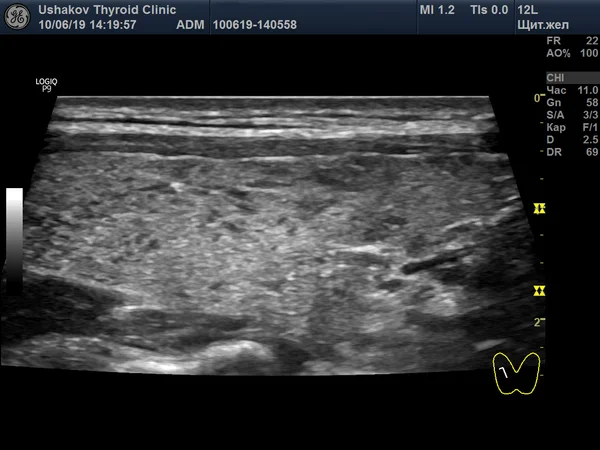

На первом снимке тёмные участки — это зоны, где ткань железы замещена лимфоидной (иммунной) тканью. Важно заметить светлые островки внутри этих зон — это и есть начавшиеся очаги регенерации.